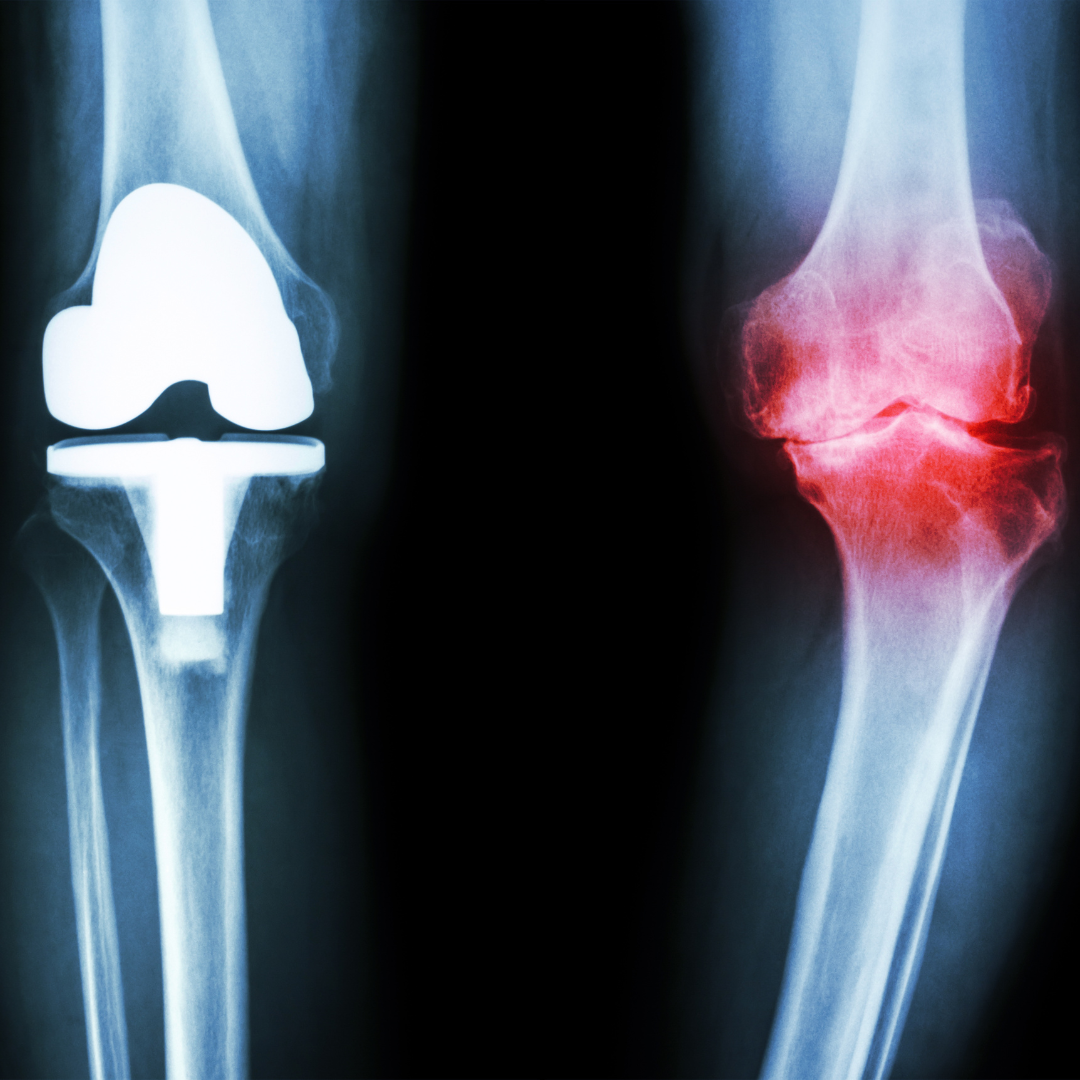

Les troubles fonctionnels digestifs (TFD) et l’arthrose, bien que distincts, partagent un socle commun : l’inflammation systémique.

1. Physiologie des TFD (troubles fonctionnels digestifs) et de l’Arthrose : Un Lien Inflammatoire